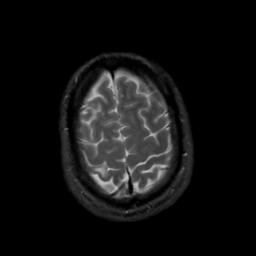

MR Study #5, March 10, 1991 -- Slice #44

[Home][Help][Clinical][Tour 1][Tour 2] Slice 44